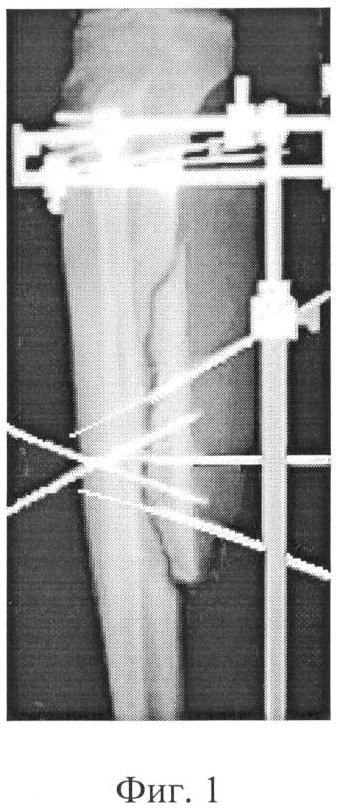

Фиг.1 – рентгенограмма голени больного после выполнения остеосинтеза согласно предложенному способу;

В ходе операции больному выполнен остеосинтез правой голени аппаратом внешней фиксации; сформирован продольный отшеп большеберцовой кости величиной 7 см. Отщеп фиксировали тракционными «биметаллическими» спицами, рабочие концы которых ввели в противостоящий отщепу участок материнской кости, а их свободные концы с возможностью осевого перемещения закрепили в трационных узлах, соединенных с опорами аппарата.

В дополнение к тракционным спицам со стороны противостоящего участка кости в кососагиттальной плоскости перекрестно ввели две спицы меньшей жесткости. Их рабочие концы внедрили в продольный отщеп до выхода из кортикального слоя, а свободные концы закрепили на дополнительной опоре.

Операцию завершили ушиванием ран, стабилизацией систем аппарата и выполнением контрольной рентгенографии.